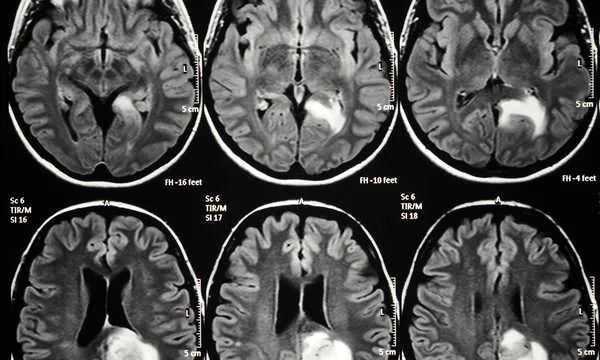

Badania naukowe z wykorzystaniem MRI dostarczyły fascynujących, choć subtelnych, wskazówek dotyczących zmian w mózgu osób ze schizofrenią. Jedną z najczęściej obserwowanych anomalii jest zmniejszenie objętości istoty szarej w różnych obszarach mózgu. Dotyczy to szczególnie takich struktur jak hipokamp (kluczowy dla pamięci i emocji), ciało migdałowate (odpowiedzialne za przetwarzanie strachu i innych emocji) oraz płaty skroniowe. Te zmiany mogą wpływać na sposób przetwarzania informacji, emocji i percepcji, co koreluje z objawami schizofrenii. Należy jednak podkreślić, że są to wyniki badań grupowych, a nie indywidualne markery diagnostyczne. Oznacza to, że nie każdy pacjent ze schizofrenią będzie miał identyczne zmiany, a sama obecność tych zmian nie wystarcza do postawienia diagnozy.

Powiększone komory mózgu czy to stały marker choroby?

Inną obserwacją, która pojawia się w badaniach nad schizofrenią, jest powiększenie komór bocznych mózgu. Komory to przestrzenie wypełnione płynem mózgowo-rdzeniowym. Ich powiększenie może być pośrednim wskaźnikiem zmniejszenia objętości tkanki mózgowej otaczającej komory. Chociaż jest to często obserwowane u pacjentów ze schizofrenią, nie jest to stałe odkrycie i nie występuje u wszystkich. Co więcej, powiększenie komór może być również związane z innymi schorzeniami neurologicznymi lub być cechą indywidualną. Z tego powodu, choć interesujące z punktu widzenia badań, samo powiększenie komór nie jest wystarczającym ani jednoznacznym markerem diagnostycznym schizofrenii w codziennej praktyce klinicznej.

Hipokamp i ciało migdałowate to dwie kluczowe struktury w układzie limbicznym, które odgrywają fundamentalną rolę w przetwarzaniu emocji, pamięci i reakcji na stres. Hipokamp jest zaangażowany w uczenie się i pamięć, a także regulację nastroju, natomiast ciało migdałowate jest centrum przetwarzania strachu i innych silnych emocji. Badania MRI wykazały, że przewlekły stres i ciężka depresja mogą prowadzić do zmian objętościowych w tych strukturach. Często obserwuje się zmniejszenie objętości hipokampa u osób z długotrwałą depresją, co może być związane z utratą neuronów lub zmniejszeniem ich plastyczności. Z kolei w zaburzeniach lękowych, zwłaszcza w zespole stresu pourazowego (PTSD), często stwierdza się nadaktywność ciała migdałowatego. Te odkrycia podkreślają neurobiologiczne podłoże tych zaburzeń i pokazują, jak doświadczenia życiowe mogą dosłownie "rzeźbić" nasz mózg.